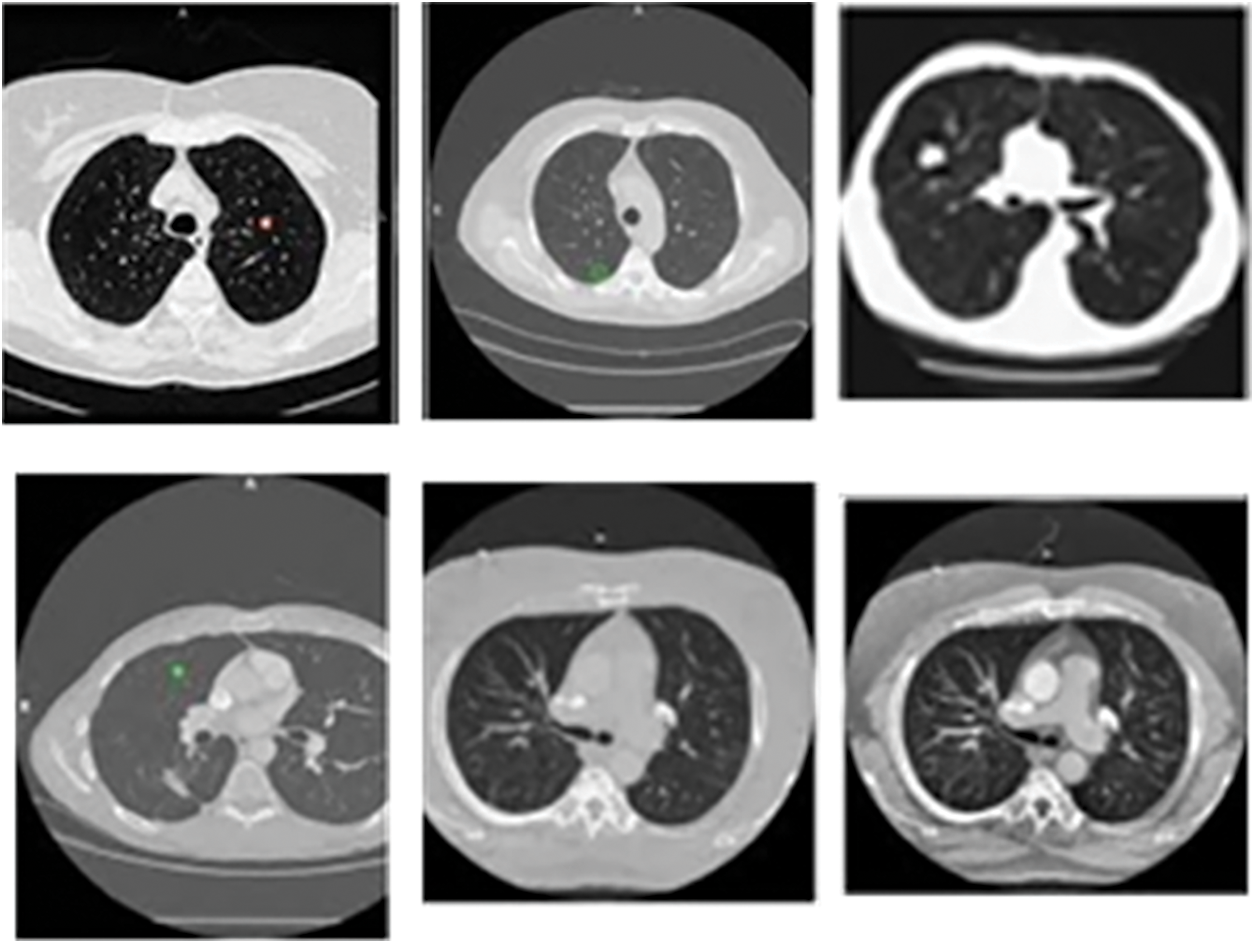

The proposed model is analyzed using the input CT images obtained from the benchmark dataset called LIDC-IDRI database dataset. The database contains lung images from 1018 patients. Moreover, the images are on three categories, namely, nodule size ≥ 3 mm, nodule size < 3 mm and non-nodule ≥ 3 mm and the sample image from the LIDC dataset is displayed in the Fig. 4.

Figure 4: Sample CT lung images from LIDC-IDRI dataset